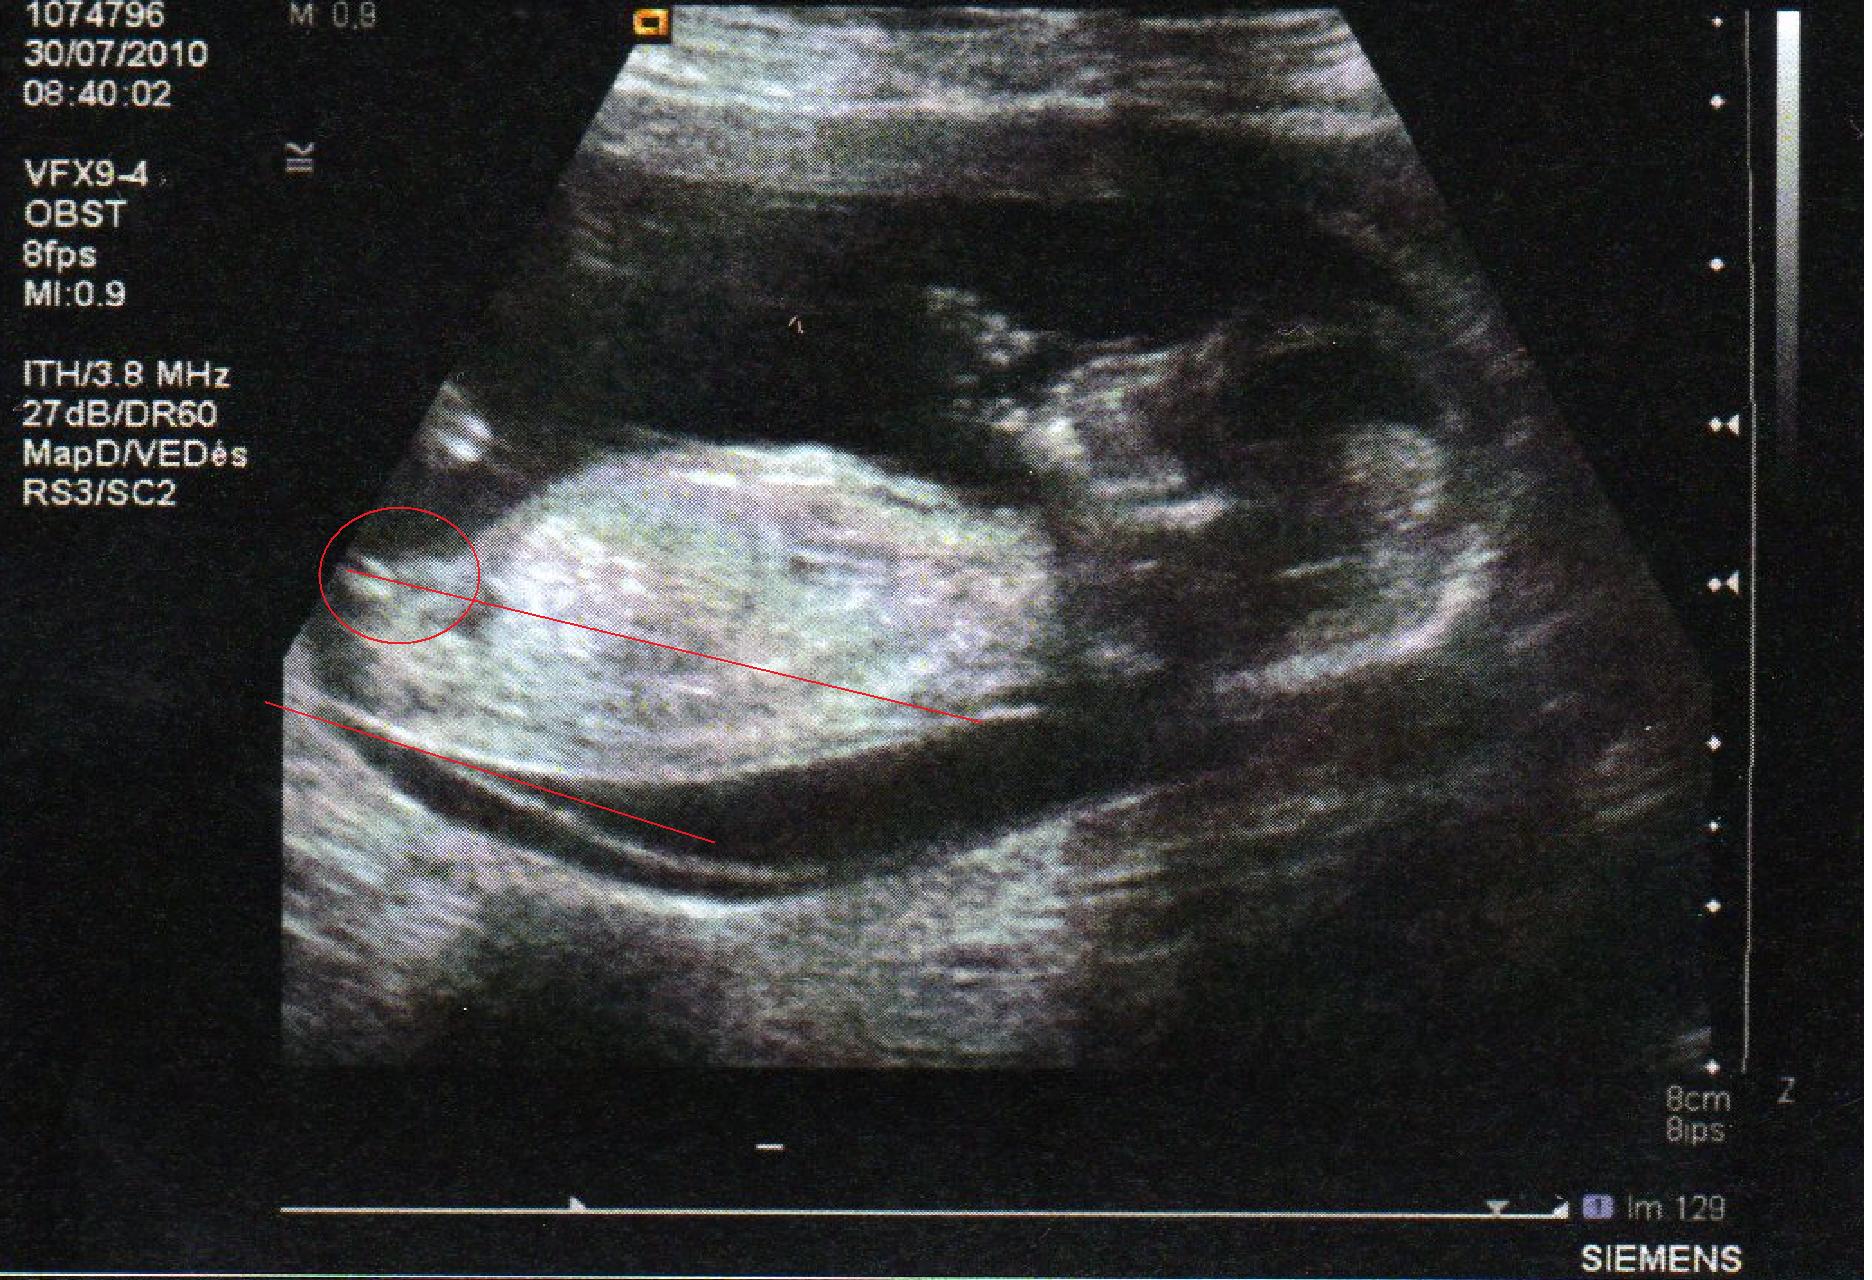

Bourgeon génital coucou les filles voici ma 1 ère écho à 13 SA on voit bien le bourgeon foetal entre les jambes, c'est le truc droit qui pointe vous en pensez quoi?Il est quand même bien horizontal, comme pour une filleOLXro iti ofera posibilitatea de a publica anunturi gratuite pentru orasul tau si imprejurimile sale Vei gasi usor pe OLXro anunturi gratuite interesante din Bucuresti, Ilfov si alte orase din tara si vei putea intra usor in legatura cu cei care leau publicat Pe OLXro te asteapta locuri de munca, apartamente si camere de inchiriat, masini secondhand si telefoane mobile la preturi mici

Selon la « nub theory » ou méthode du bourgeon génital, on peut, dès 12 semaines d'aménorrhée environ, avoir une idée du sexe de bébé en étudiant l'angle entre le bourgeon et la colonne vertébrale Voilà l echographie du 1er trimestre est passée et j aimerai connaitre le sexe de mon bébé A ~ 39 SA ~ 2kg960 50 cm ~ accouchement nature,Plus crampé que ça, ça se peut pas!!!Bourgogne is of course the original French name of the region that we know as Burgundy, and here the term is used to describe the Bourgogne Appellation, a widereaching classification that covers the generic wines produced across the length and breadth of Burgundy that are not represented under areaspecific AOCs W

Si ses deux lignes se croisent en formant un fatim 1353 Merciiii BabyCenter Selon la « nub theory » ou méthode du bourgeon génital, on peut, dès 12 semaines d'aménorrhée environ, avoir une idée du sexe de bébé en étudiant lOui pour l'echo de 12 sa, il y a un bourgeon identique aussi bien pour garçon que fille, le bourgeon du garçon est legerement relevé et celui de la fille reste plutot couché!Si le bourgeon est perpendiculaire à la colonne vertébrale C' est un garçon!

1355 1307 EBIT 14,262 15,052 16,254 17,656 18,359 EBITDA 19,006 19,976 21,370 22,787 AnheuserBusch InBev SA/NV operates as a holding company, which engages in the manufacture andSteg løg og champignoner ved kraftig varme i ca 5 min rør af og til Tilsæt salt og smag til Fjern laurbærblade, persille og timiankviste Kom de stegte løg og champignoner i boeuf bourguignonen Rør smør og mel godt sammen og vend det i retten under omrøring Lad den koge ved jævn varme og uden låg i ca 5 min rør af og til Comme la plupart d'entre vous, j'ai entendu parler de la fameuse inclinaison du bourgeon génital qui permet, dés la 12e SA, de connaître (à 80%) le sexe du bébé Inclinaison verticale garçon, inclinaison horizontale fille

Ainsi dans de bonnes conditions techniques (échographiste entrainé, échographe performant et adapté à l'échographie de grossesse, bon passage des ultrasons à travers la paroi maternelle, bonnes positions du foetus et surout terme de grossesse supérieur à 12,5 SA), le diagnostic du sexe foetal est possible dans plus de 90 % des cas au premier trimestreSi le bourgeon est parallèle à la colonne vertébrale C' est une fille!Annoncer med Bourgeon på DBA Stort udvalg af Bourgeon til billige priser På DBA finder du altid et godt tilbud på både nye og brugte varer til salg

Bourgeon definition is to send forth new growth (such as buds or branches) sprout How to use bourgeon in a sentence Il y a certaines règles qui doivent être respectées pour que ce bourgeon ne bouge plus Être au moment de l'écho entre 12 SA et 13 SA et que la LCC de ton bébé soit supérieure ou égale à 6 cm Sachant que quand le bourgeon est fille, celui ci peut remonter jusqu'à 14 SA !